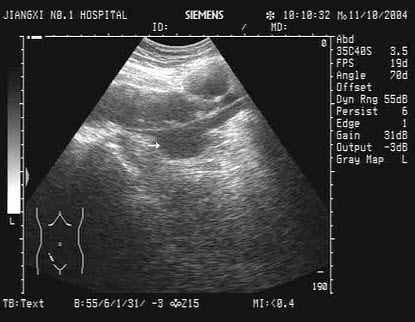

35、单项选择题

男,48岁,上腹胀痛,纳差,血吸虫病多年。结合超声声像图,诊断为()

A.血吸虫肝纤维化

B.脂肪肝

C.细菌性肝脓疡

D.肝豆状核变性

E.肝炎